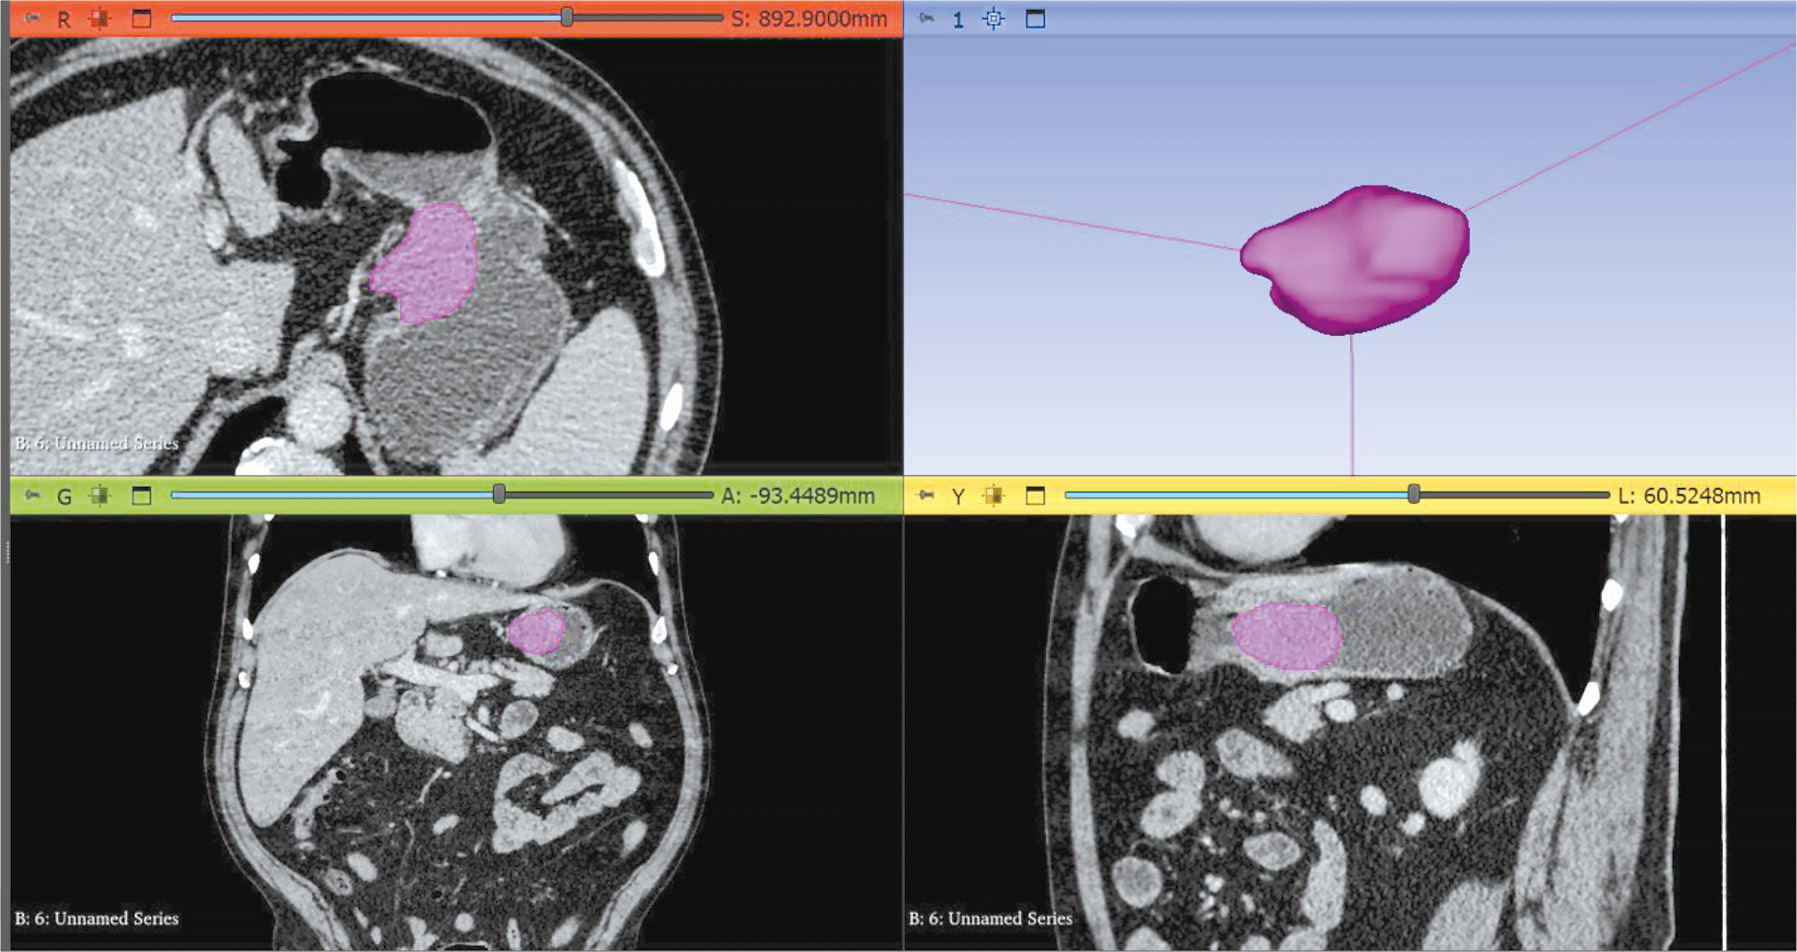

BACKGROUND: Artificial intelligence algorithms are used to analyze images obtained through radiological diagnostic methods. The effectiveness of such algorithms depends on the availability of relevant and representative training datasets. The volume of such data in the public domain should be increased, particularly datasets containing abdominal aorta computed tomography angiography images, with pathology classification and vessel segmentation. The limitations of existing solutions include small sample sizes, restricted dataset specialization, and inconsistent dataset preparation methodologies.

Aim: To create an open dataset containing computed tomography angiography images of abdominal aorta segmentation for normal aorta, aneurysm, thrombosis, and calcification.

MATERIALS AND METHODS: A technical specification for dataset preparation was developed according to the methodology for testing artificial intelligence algorithms, the required sample size was calculated, and approval was obtained from an independent ethics committee. Regarding dataset creation, a previously developed original semiautomatic segmentation algorithm using Slicer 3D software was employed. The inclusion criteria were computed tomography angiography or abdominal computed tomography scans with contrast, arterial phase, and slice thickness ≤3 mm. Conversely, the exclusion criteria were presence of foreign bodies in the aorta lumen and aortic dissection. The algorithm was tested on patient data obtained from the Unified Radiological Information System. An expert evaluation was conducted to assess the compliance of obtained results with the established requirements and evaluate the time efficiency of using the developed segmentation algorithm.

RESULTS: The calculated sample size was 100 angiographic studies, including arterial phase scans with a slice thickness of ≤1.2 mm. Population data: number of unique patients, 100; percentage of female patients, 51%; and median age, 62 years (age range: 18–84 years). Pathology (including combined pathology) was detected in 61% of cases: 60 studies showed signs of calcification, 18 revealed aortic dilation, and 18 determined signs of thrombosed lumen. The average time to process one study (100 slices) using the developed segmentation algorithm was 0.8 hours.

CONCLUSIONS: A dataset containing 100 computed tomography angiography results with abdominal aorta segmentation for normal cases, aneurysm, thrombosis, and calcification was created. The dataset is publicly available and can be used for developing and testing artificial intelligence algorithms and for anthropomorphic modeling of the abdominal aorta.